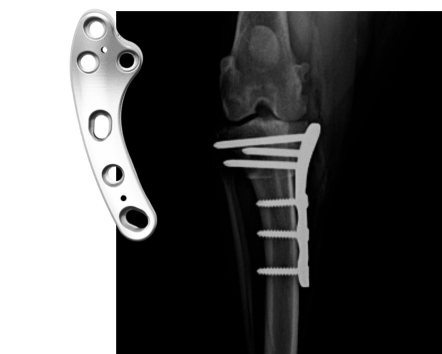

Our introductory TPLO workshops are designed to give veterinarians a solid foundation in the procedure from day one. You’ll learn how to evaluate patients, plan and execute the surgery step by step using the BioCurve TPLO plate, and understand the principles behind successful outcomes. Through guided lectures and hands-on cadaver labs, you’ll gain the technical confidence and clinical judgment needed to approach your first TPLO cases with confidence.

For veterinarians already performing TPLO, our advanced workshops are designed to expand your skills and deepen your clinical confidence. You’ll explore challenging case selection, learn strategies for preventing and managing complications, and refine your surgical approach under expert guidance. With practical labs and direct instructor feedback, these workshops prepare you to handle complex scenarios.

✓ Advanced application of locking plate systems